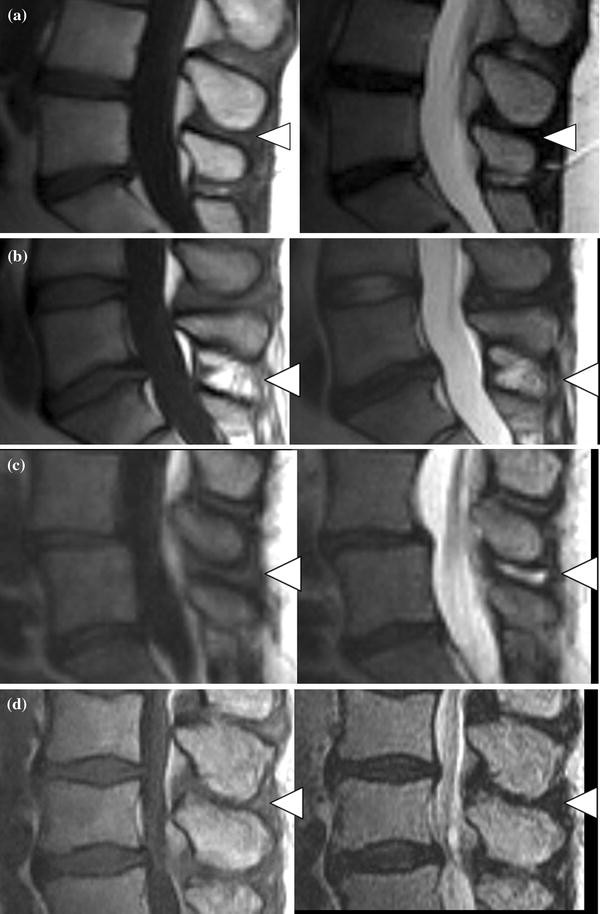

The lumbar spine MR images were assessed independently by three spine surgeons with 3, 7, and 9 years of experience with lumbar spine MRI. Each reader analyzed the images on separate occasions after the selected images were randomly reordered, with a minimum interval of 1 week. Instructions explaining the classification system and a set of sample images were given to all readers during the review (Fig. 1). All readers were instructed to precisely follow the classification algorithm.

Example of each grade of interspinous ligament degeneration (arrowhead). a Grade A low- to iso-signal intensity on T1- and T2-weighted images. b Grade B high signal intensity on T1- and T2-weighted images. c Grade C low signal intensity on T1-weighted images and high signal intensity on T2-weighted images. d Grade D low or iso-signal intensity on T1- and T2-weighted images with marked narrowing of the interspinous interval